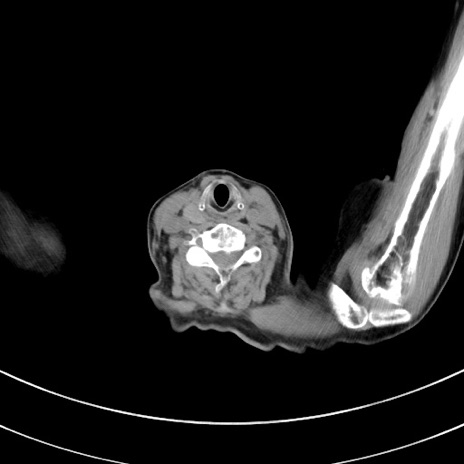

冠状断像